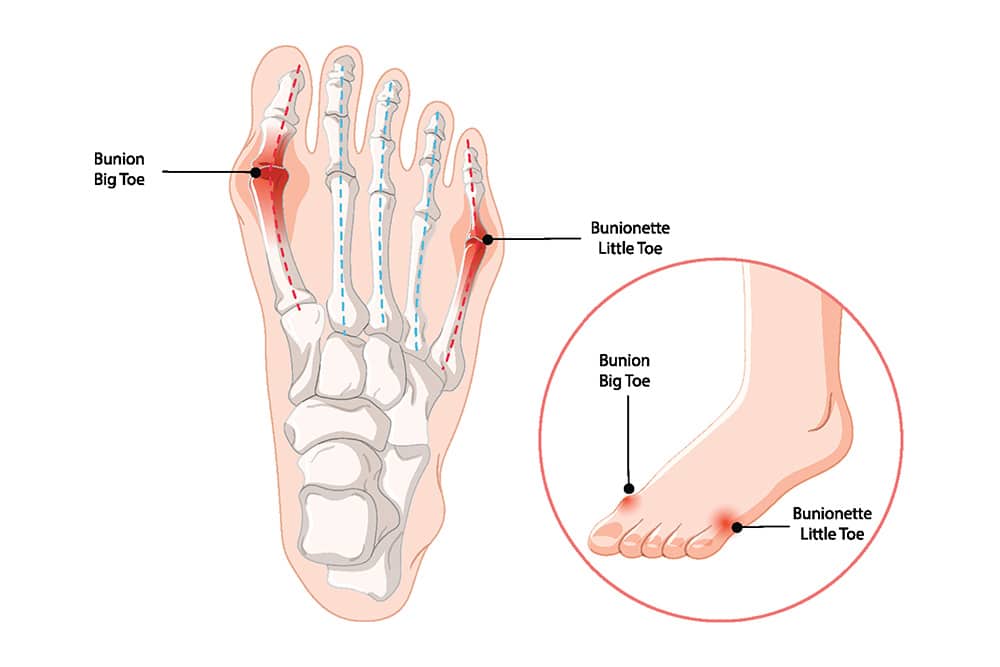

A bunion is also known as hallux valgus, a condition that develops when the big toe begins angling towards the second toe and the joint at its base becomes more prominent. However, a similar bump can also develop at the base of the little toe (the fifth MTP), which is known as a bunionette or Tailor’s Bunion. So, before you decide on the most appropriate treatment option, it helps to know which type you are dealing with, and how far it has progressed.

This is the most common type of bunion, where the bump forms at the base of the big toe and becomes more prominent as the toe angle increases.

A bunionette forms at the base of the little toe, on the outer side of the forefoot. In many cases, it becomes noticeable when footwear pressure or repeated rubbing irritates the joint area over time. As the bump becomes more prominent, pain and inflammation can start showing up more often, especially in snug shoes.

A bunion happens when the big toe gradually drifts toward the second toe and the joint at its base becomes more prominent. As alignment shifts, the bump can enlarge, and shoes often start pressing against the side of the forefoot. A similar deformity can also form at the little toe joint, which is called a bunionette. Although the bump is what you notice first, the underlying issue is bone and joint misalignment that continues shifting under everyday load.

Bunions often worsen over time because the joint continues taking load while the toe remains out of alignment. As the deformity progresses, pain can become more frequent, and finding shoes that fit comfortably can become more difficult. In more severe cases, the big toe can crowd the smaller toes, increasing pressure through the forefoot and contributing to hammer toe changes over time. A bunionette can also become more symptomatic when rubbing and compression persist along the outer side of the foot, especially in snug footwear.